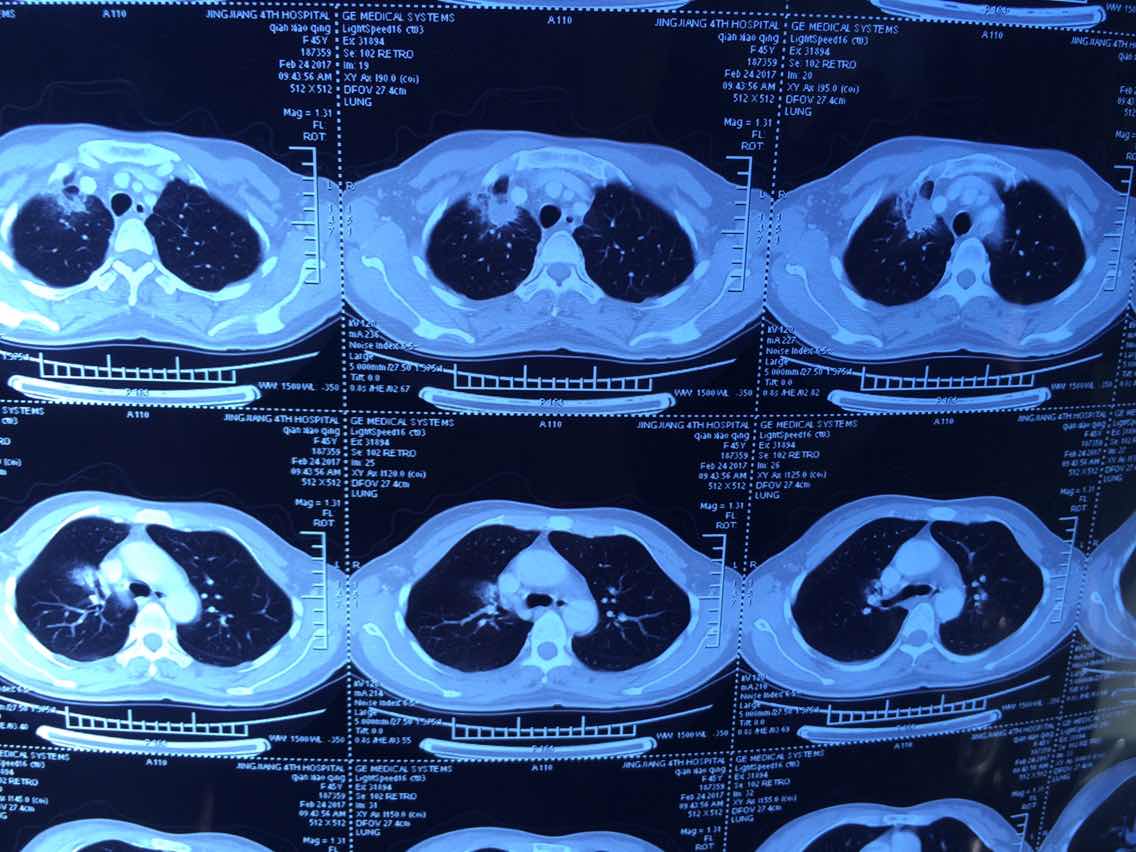

2017.2.24的

举报

2017-10-31 10:13:10 有用(0)

回复(0)

2

2017-10-31 10:14:04 有用(0)